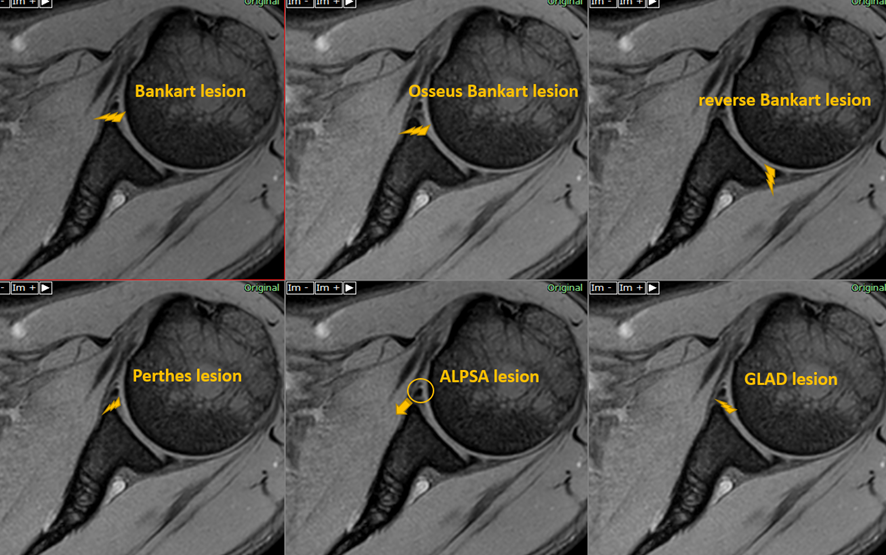

股関節唇裂傷の種類

唇裂傷は、裂ける場所に応じて大きく2つに分類されます。

- 前部の涙。これらは腹部に最も近い関節側に発生します。

- 後部の涙。これらは背中に最も近い関節の側に発生します。

によると、断裂の大部分は関節唇の前面で発生し、後面よりも幅が広くて薄いです。